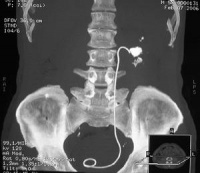

肾与输尿管结石

90%以上的输尿管结石在尿路平片上可被显示,草酸钙显示最佳,但需与腹腔淋巴结钙化盆腔静脉石阑尾粪石和骨岛角相鉴别。静脉尿路造影主要了解结石的部位和肾功能与有无积水,必要时行大剂量尿路造影及放射性核素肾图检查,均能进一步了解肾功能情况。膀胱镜检查与输尿管插管在结石处受阻,并拍平片钙化阴影在导管的同一平面,即能肯定输尿管结石的诊断。阴性结石用空气为对比剂作逆行造影摄片,则可显示结石的存在。另外CT及B型超声检查有助于对X线平片不显影结石的诊断。

2.泌尿系X线平片:在输尿管的途径上显出结石影。

3.尿路造影:在输尿管内显出结石影。

5.超声检查:在输尿管行程上显出结石。